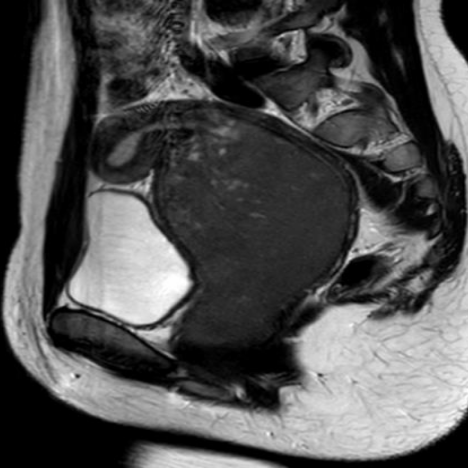

16岁花季少女,第二性征发育及营养状况良好,无躯体及头面部发育畸形,至今竟无月经来潮,完善经腹部超声提示盆腔探及囊性暗区71*68mm,逐步完善盆腔MRI及经直肠超声、专科检查,揭开了神秘的面纱。